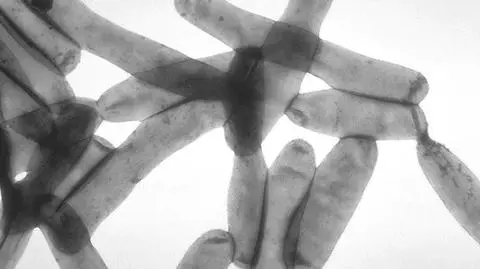

Bakterie Legionella pneumophila

Legioneloza to choroba układu oddechowego. Jest chorobą zakaźną, ale nie zaraźliwą. Wywołują ją bakterie Legionella, które występują w wodzie i rozmnażają się w temperaturze 20-50 stopni Celsjusza.

Legioneloza nie przenosi się z człowieka na człowieka. Stanowi zagrożenie dla ludzi jedynie, gdy dostanie się do dróg oddechowych. Do zakażenia może dochodzić poprzez wdychanie powietrza, w którym znajduje się aerozol skażonej bakteriami wody (mgła wodna powstała w wyniku rozprysku wody). Legionella nie przenosi się też drogą pokarmową, tzn. nie jest niebezpieczna, gdy trafi do układu pokarmowego wraz z wypitą wodą.